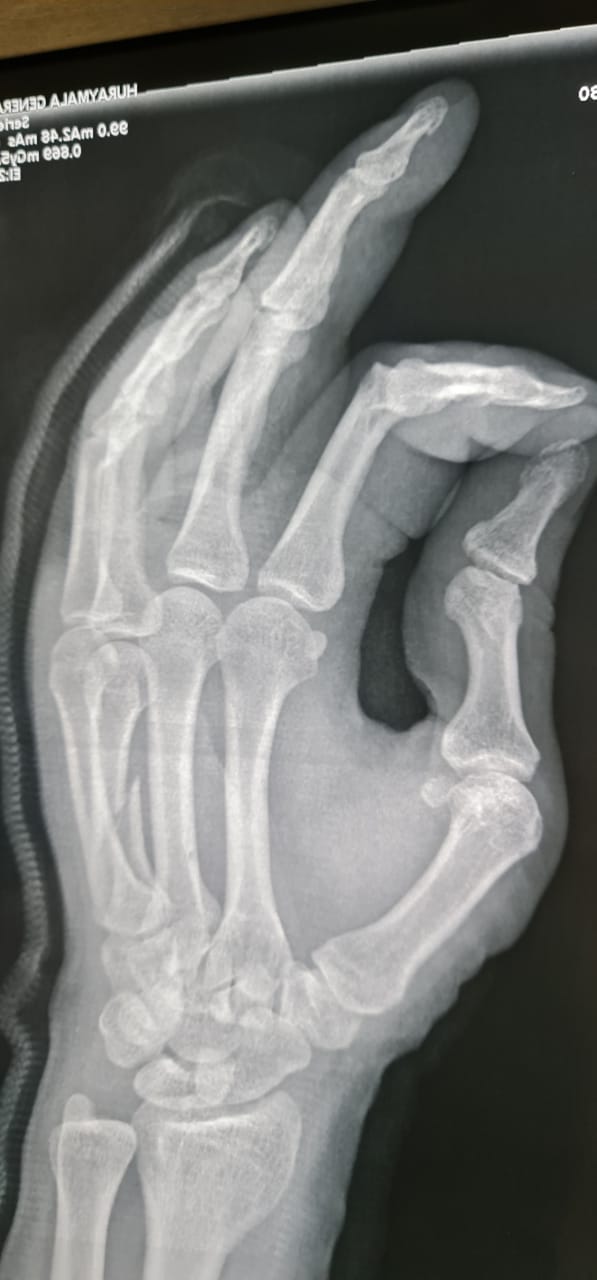

واستقبل قسم الطوارئ بالمستشفى المصاب حيث تم على الفور تشكيل فريق طبي مكون من أخصائيين قسم جراحة العظام والكسور بالمستشفى ، وقام الأطباء على الفور بعمل الإسعافات الأولية وإعطائه المحاليل والمسكنات والمضادات الحيوية، وتم عمل الأشعات العادية والمقطعية، التي أظهرت أن المريض يعاني من كسر متزحزح بالمشطية الرابعة لليد اليمنى ويحتاج تصليح مفتوح للكسر وتثبيت بشريحة ومسامير ذات طابع خاص، فتم نقل المريض إلى غرفة العمليات وإجراء عملية تثبيت بشرائح ومسامير.